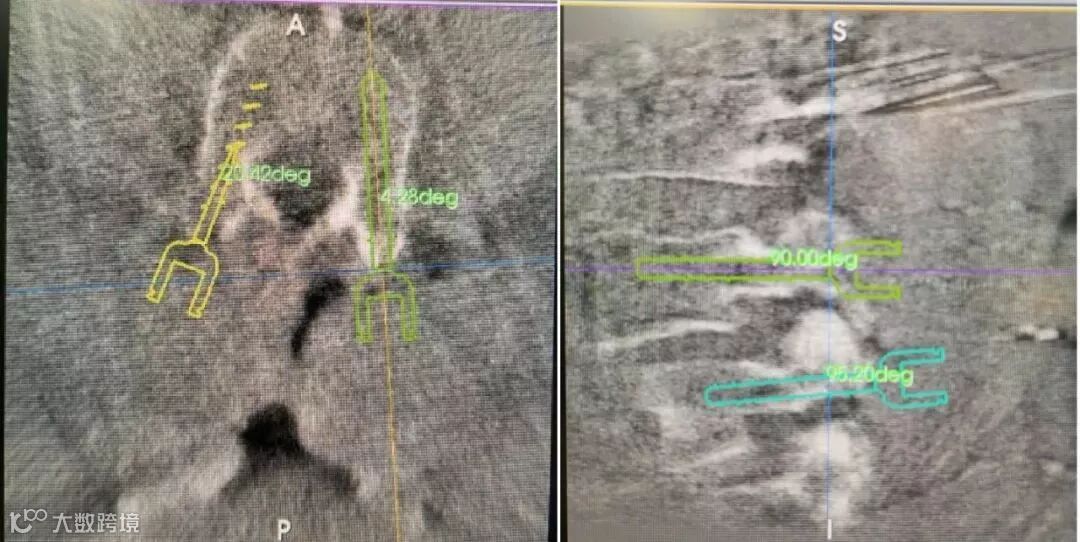

第一步:术中影像设备——术中三维C型臂对患者进行腰椎影像扫描及三维重建,图像被同步传输至骨科手术机器人系统。

第二步:医生在操作系统上规划好螺钉的角度、方向、长度及直径等关键因素后,机械臂自动到达医生设计的理想位置。

第四步:医生对患者再次进行扫描,确认螺钉的精准一致。